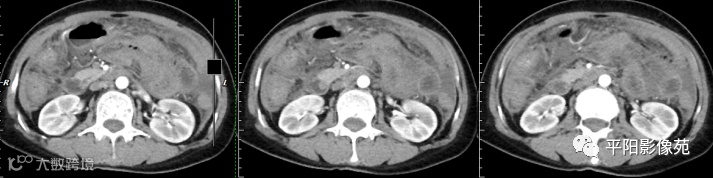

腹部增强 动脉期

壁腹膜增厚伴或不伴腹水;增厚的腹膜光滑、均匀,呈线带状,部分可见腹膜结节,网膜及肠系膜广泛浸润性改变;增强扫描明显强化。

合并淋巴结肿大,可钙化,若中心干酪样坏死,增强扫描环形强化

湿型:渗出性高密度腹水(CT值20-45HU),高密度由于高蛋白和细胞含量多可能。